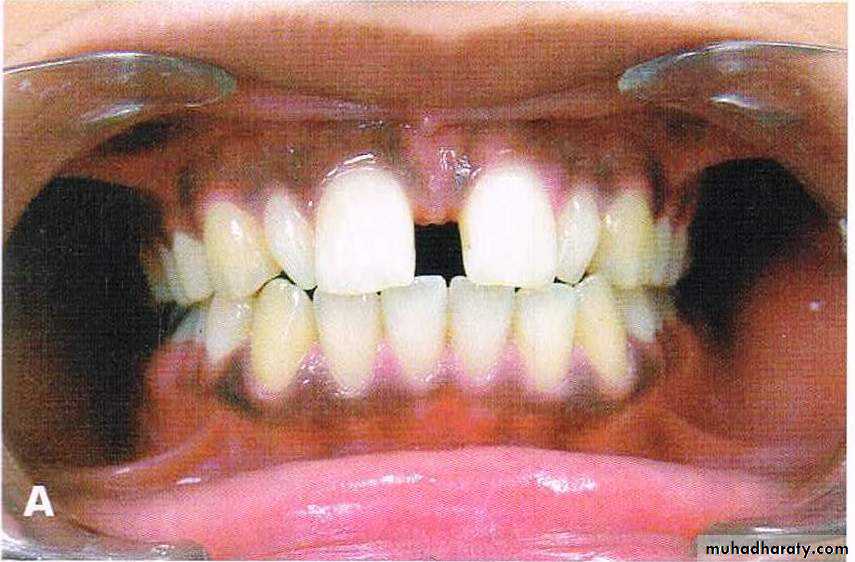

Dental spacing

Fig: Spacing73